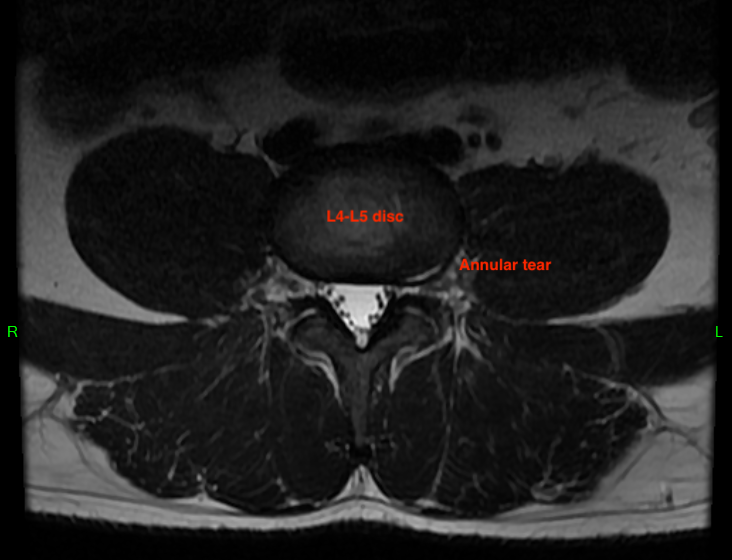

Moving down to my L4-L5 disc, you'll observe a different situation. As I said earlier, I never had any imaging done during my disc herniation in 2008, but I am reasonably certain it occurred at this level. There's no obvious hernation, but the disc's center (nucleus pulposus) is darker in color than at the L3-L4 level. Darker material has less water content and is a sign of disc degeneration. There's also a small left-side tear in the outer ring (annulus fibrous) which is a series of ligaments that connect adjacenct vertebra and contains the nucleus pulposus. Again, this isn't causing me pain, but could easily become a problem in the future. If you are pain-free and see something like this on your MRI report, take it seriously.

(L4-L5 Axial MRI)